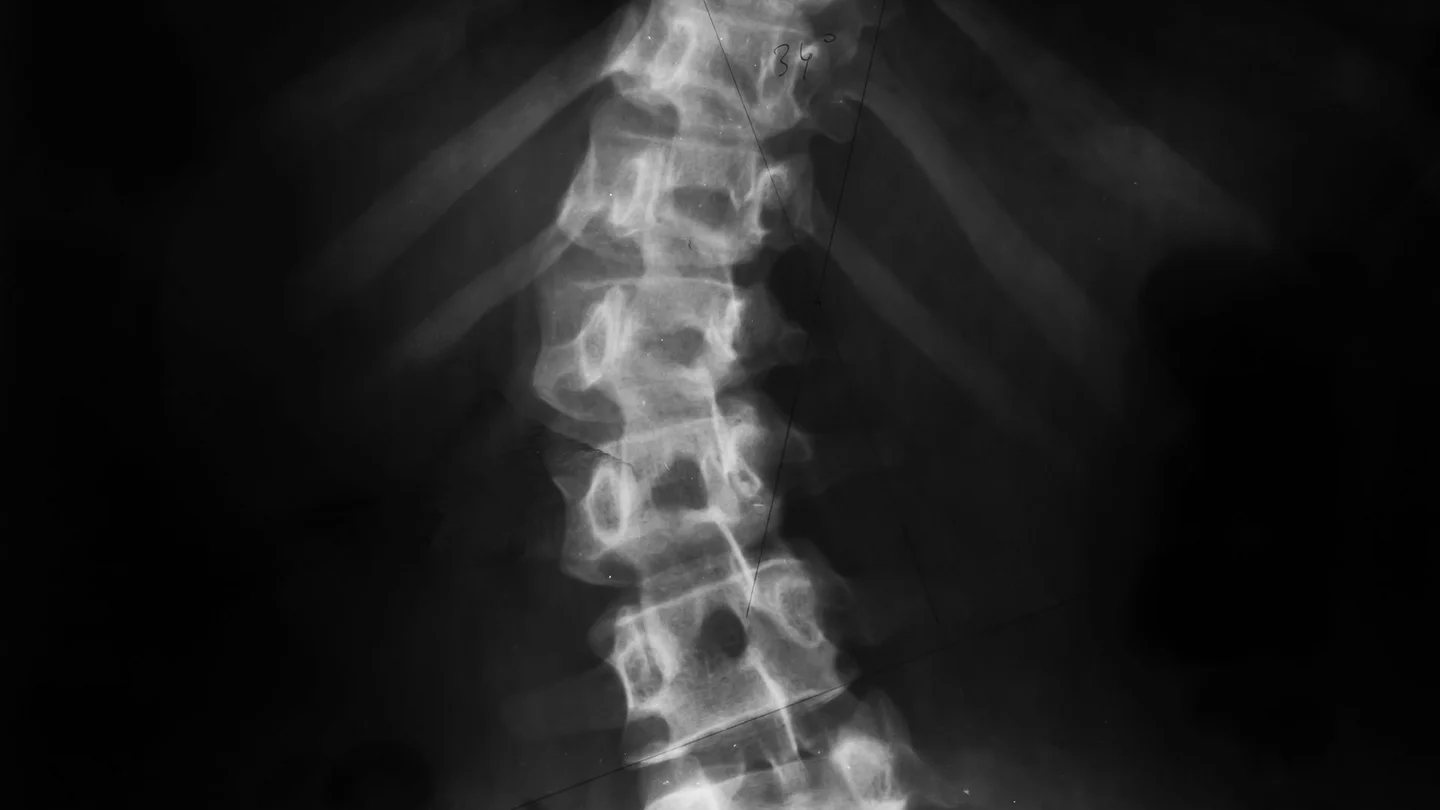

Skoliose: das schwarz-grau-weiße Röntgenbild einer Wirbelsäule Skoliose: das schwarz-grau-weiße Röntgenbild einer Wirbelsäule

قد يكون العمود الفقري متحدبًا بدرجات متفاوتة في حالة الجنف. وتسمى درجة الانحناء بزاوية كوب، ويتم تحديدها باستخدام صورة الأشعة السينية.

• التصوير بالأشعة السينية للعمود الفقري في وضعية الوقوف: توضح الصورة مدى شدة التحدب، وتستخدم لتحديد زاوية كوب.